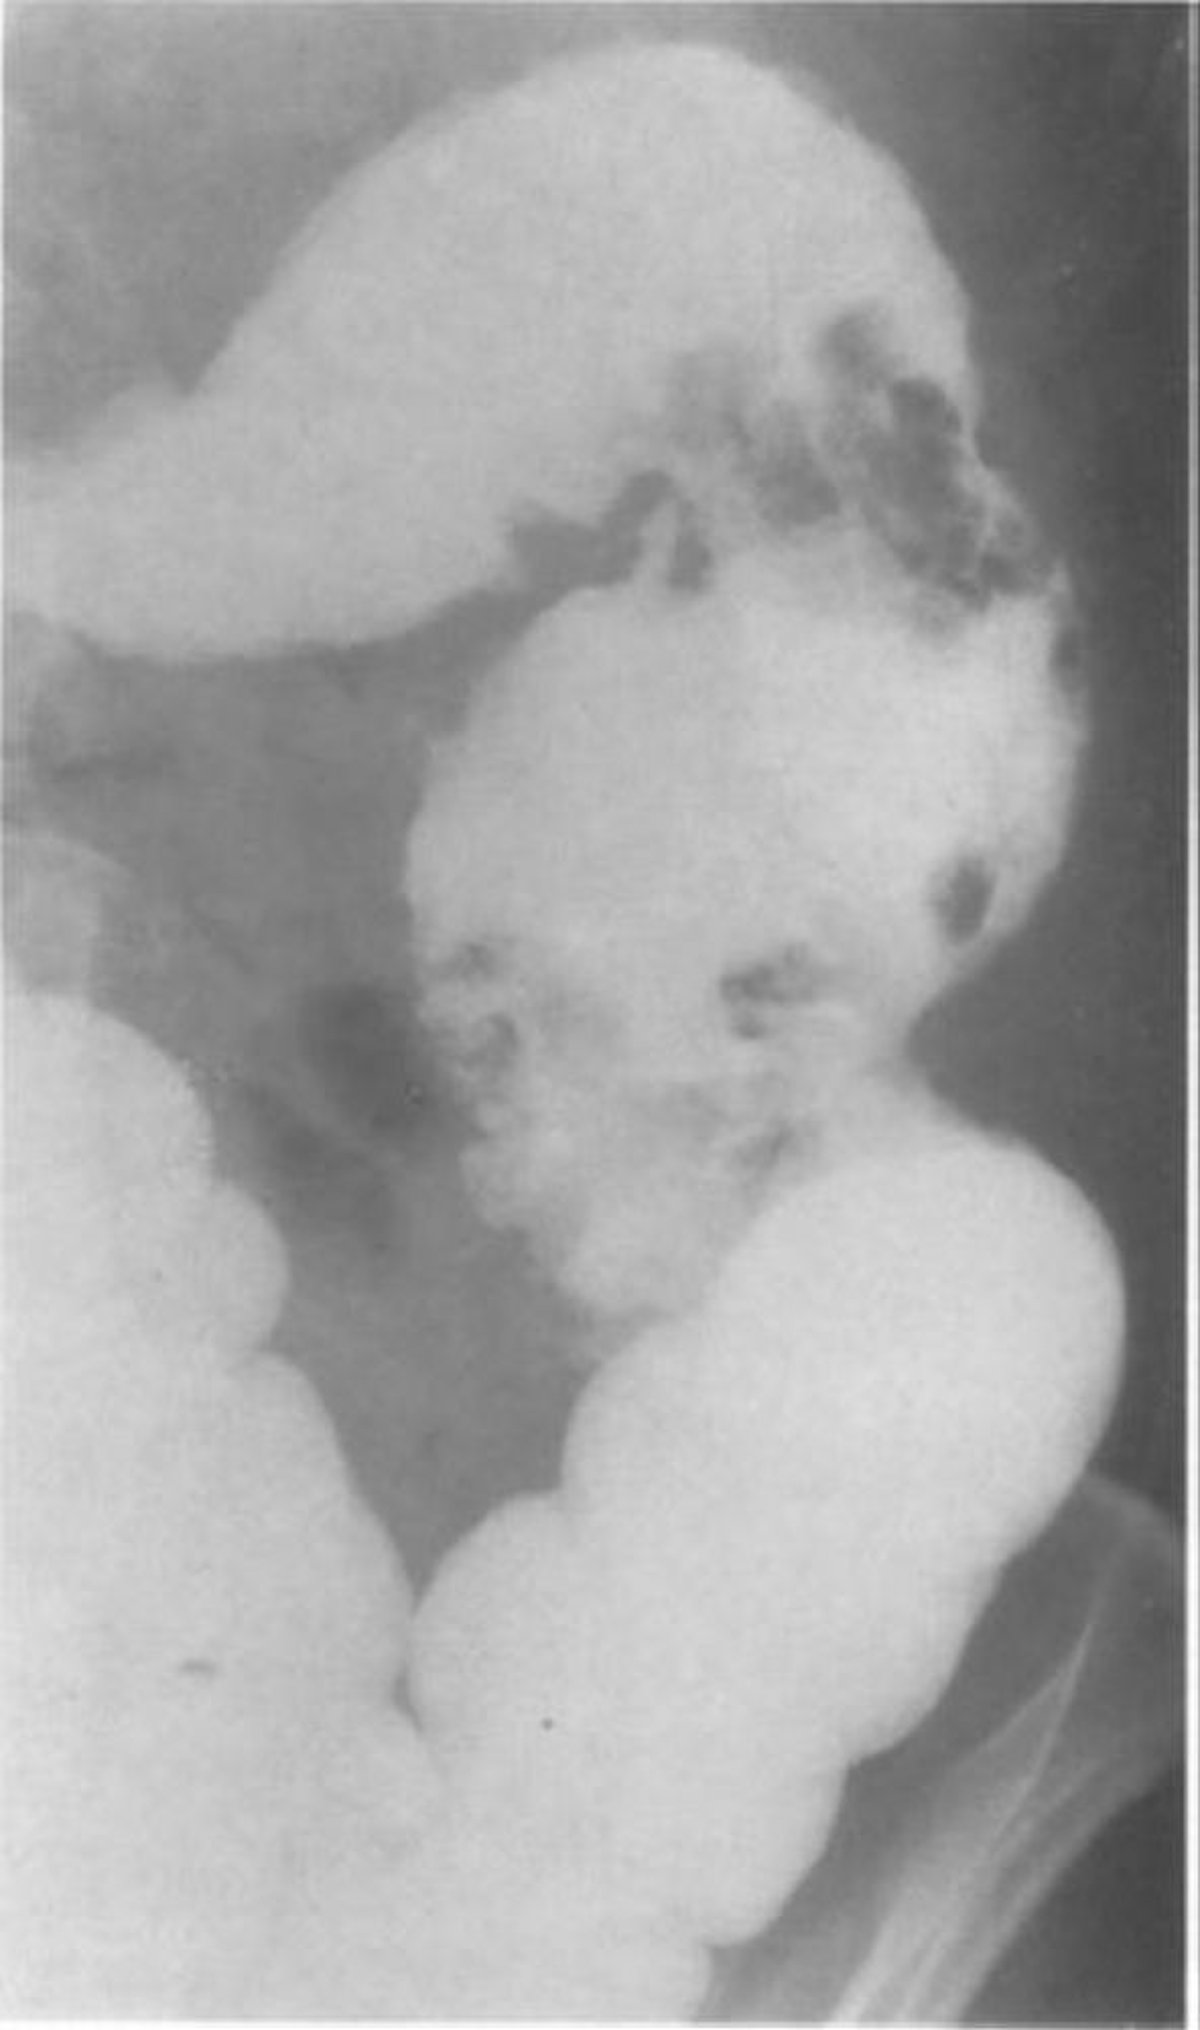

Enema de bario con seudopolipos mucosos

Esta imagen de un paciente con colitis granulomatosa muestra 2 grupos de seudopólipos de gran tamaño en el colon descendente.